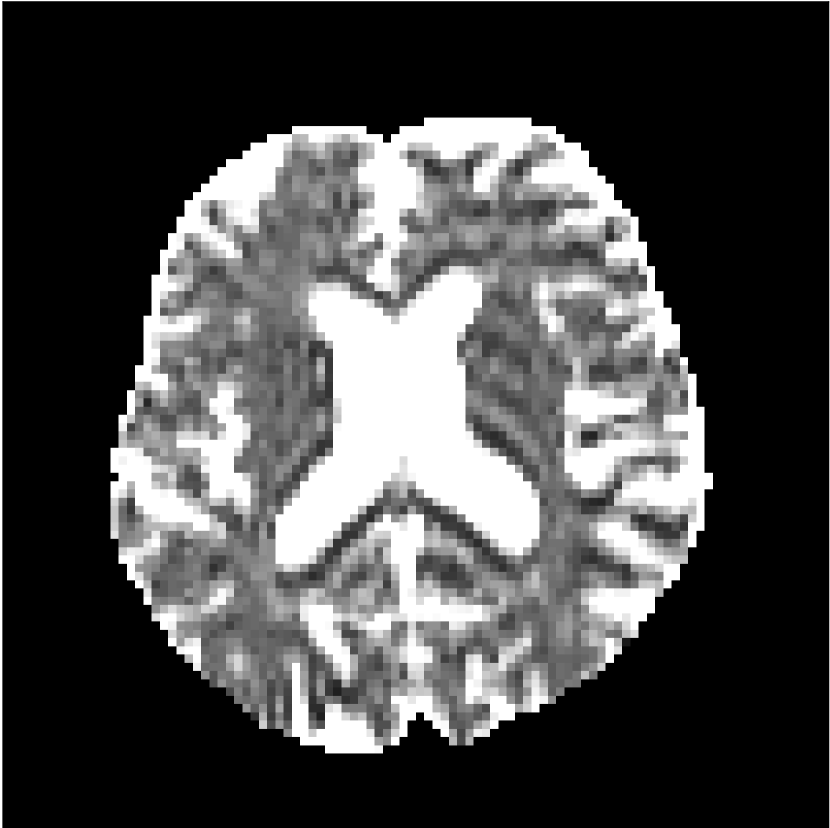

Figure 10 compares mean diffusivity maps across various partial Fourier factors between the CCNN and state-of-the-art methods.

No PF

7/8 PF

6/8 PF

5/8 PF

SoA

MD, m2/ms

CCNN

The methods perform similarly without partial Fourier acceleration, but as partial Fourier acceleration increases, the image is continually degraded in the SoA method, with "black voxels" appearing around the lateral ventricles. The CCNN method mitigates the appearance of these artifacts in the parameter maps.